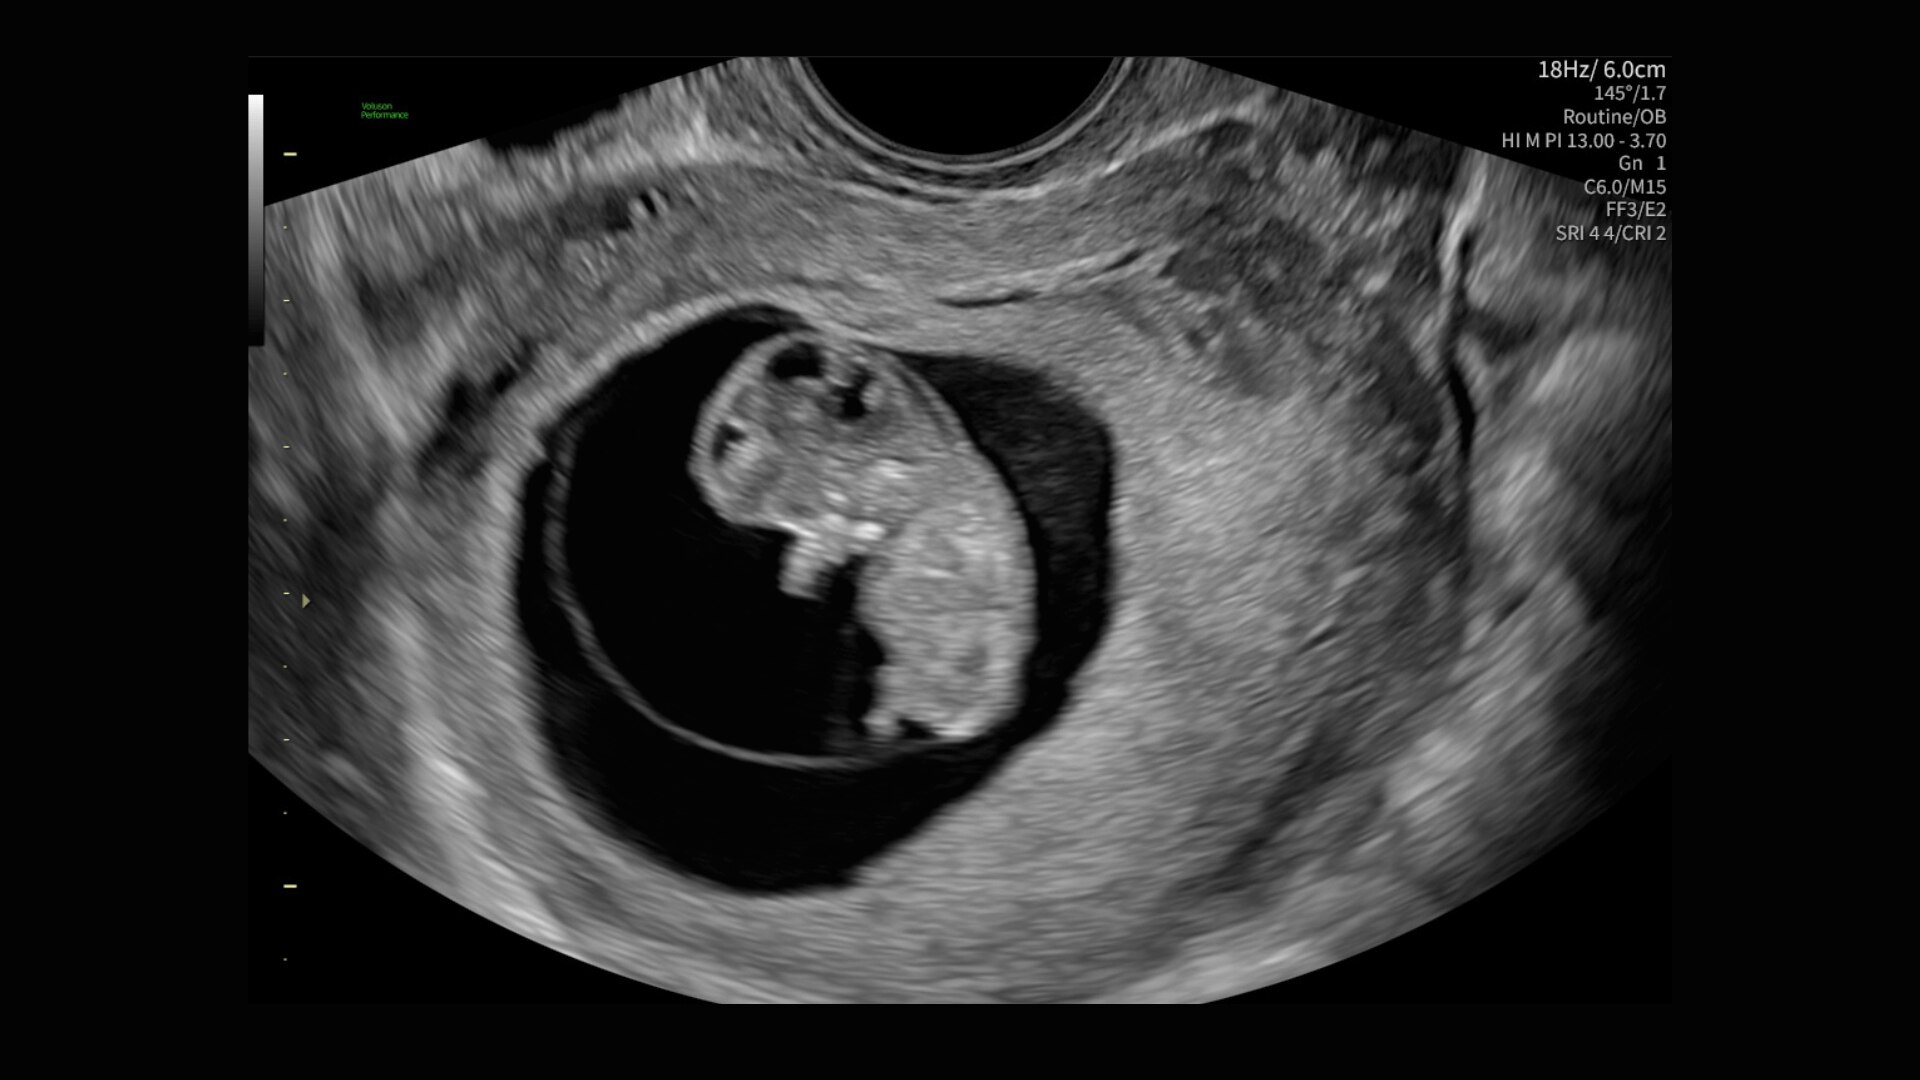

Voluson takes our commitment to women’s health ultrasound even further with the next evolution of the Voluson Performance series. It builds on its strengths, combining powerful, modern advancements with the reliability you trust. One-touch image optimization, time-saving automation, and highly-intuitive tools—it’s everything you need, in one perfect package.

The Voluson Performance 18 delivers high-resolution, detailed imaging with one-touch optimization for effortless scanning—helping you deliver quick, confident answers across a wide range of patient.